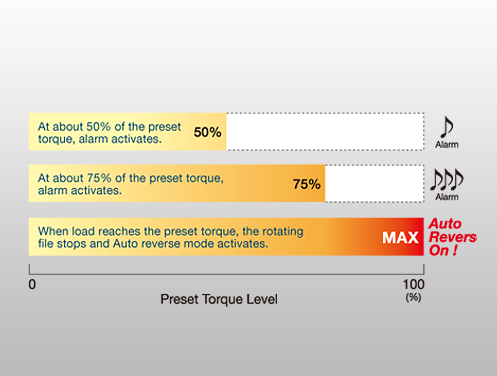

Two kinds of alarm sound for safer and efficient treatment (For ENDO-MATE TC2).